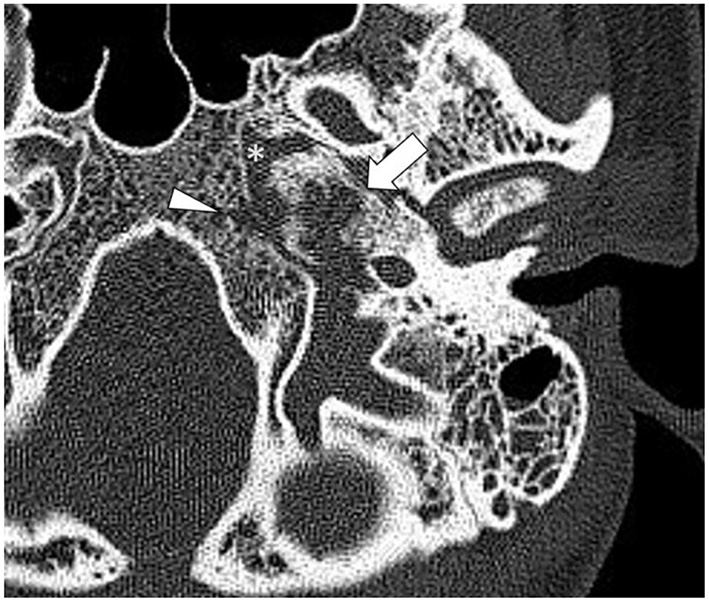

High-resolution computed tomography (HRCT) of the skull base demonstrated an aggressive erosive disease process centered on the left petrous apex involving the petroclival fissure and inferolateral clivus (Figure 1). Subsequent magnetic resonance imaging (MRI) revealed a trans-spatial marrow-replacing tumor-like soft tissue lesion of low T1/T2 signal (Figure 2A) and mild apparent diffusion coefficient (ADC) reduction. The lesion was enhanced avidly following gadolinium contrast administration (Figure 2B). Focal pachymeningeal thickening of the retroclival dura and enhancement of the cisternal segment of the left abducens nerve as it enters Dorello's canal were present.

Figure 1

Axial high-resolution computed tomography (HRCT) of the skull base shows a destructive process in the petrous apex (arrow) with regional sclerosis involving the petroclival fissure (asterisk) and clivus (arrowhead).